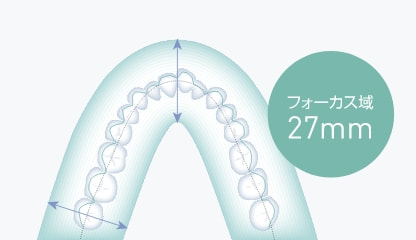

患者さんの位置付けによる撮り直しのリスクを幅広いフォーカス域を備えることで軽減。

3Dオートフォーカス技術により27mmのフォーカス域から歯列全体にピントの合ったパノラマ画像を簡単に取得できます。

3Dオートフォーカス技術でのフォーカス域

フォーカス域27mmの断層情報により歯列弓形態の個人差や位置付け時のズレにも柔軟に対応し、歯列全体にピントの合った画像が得られます。